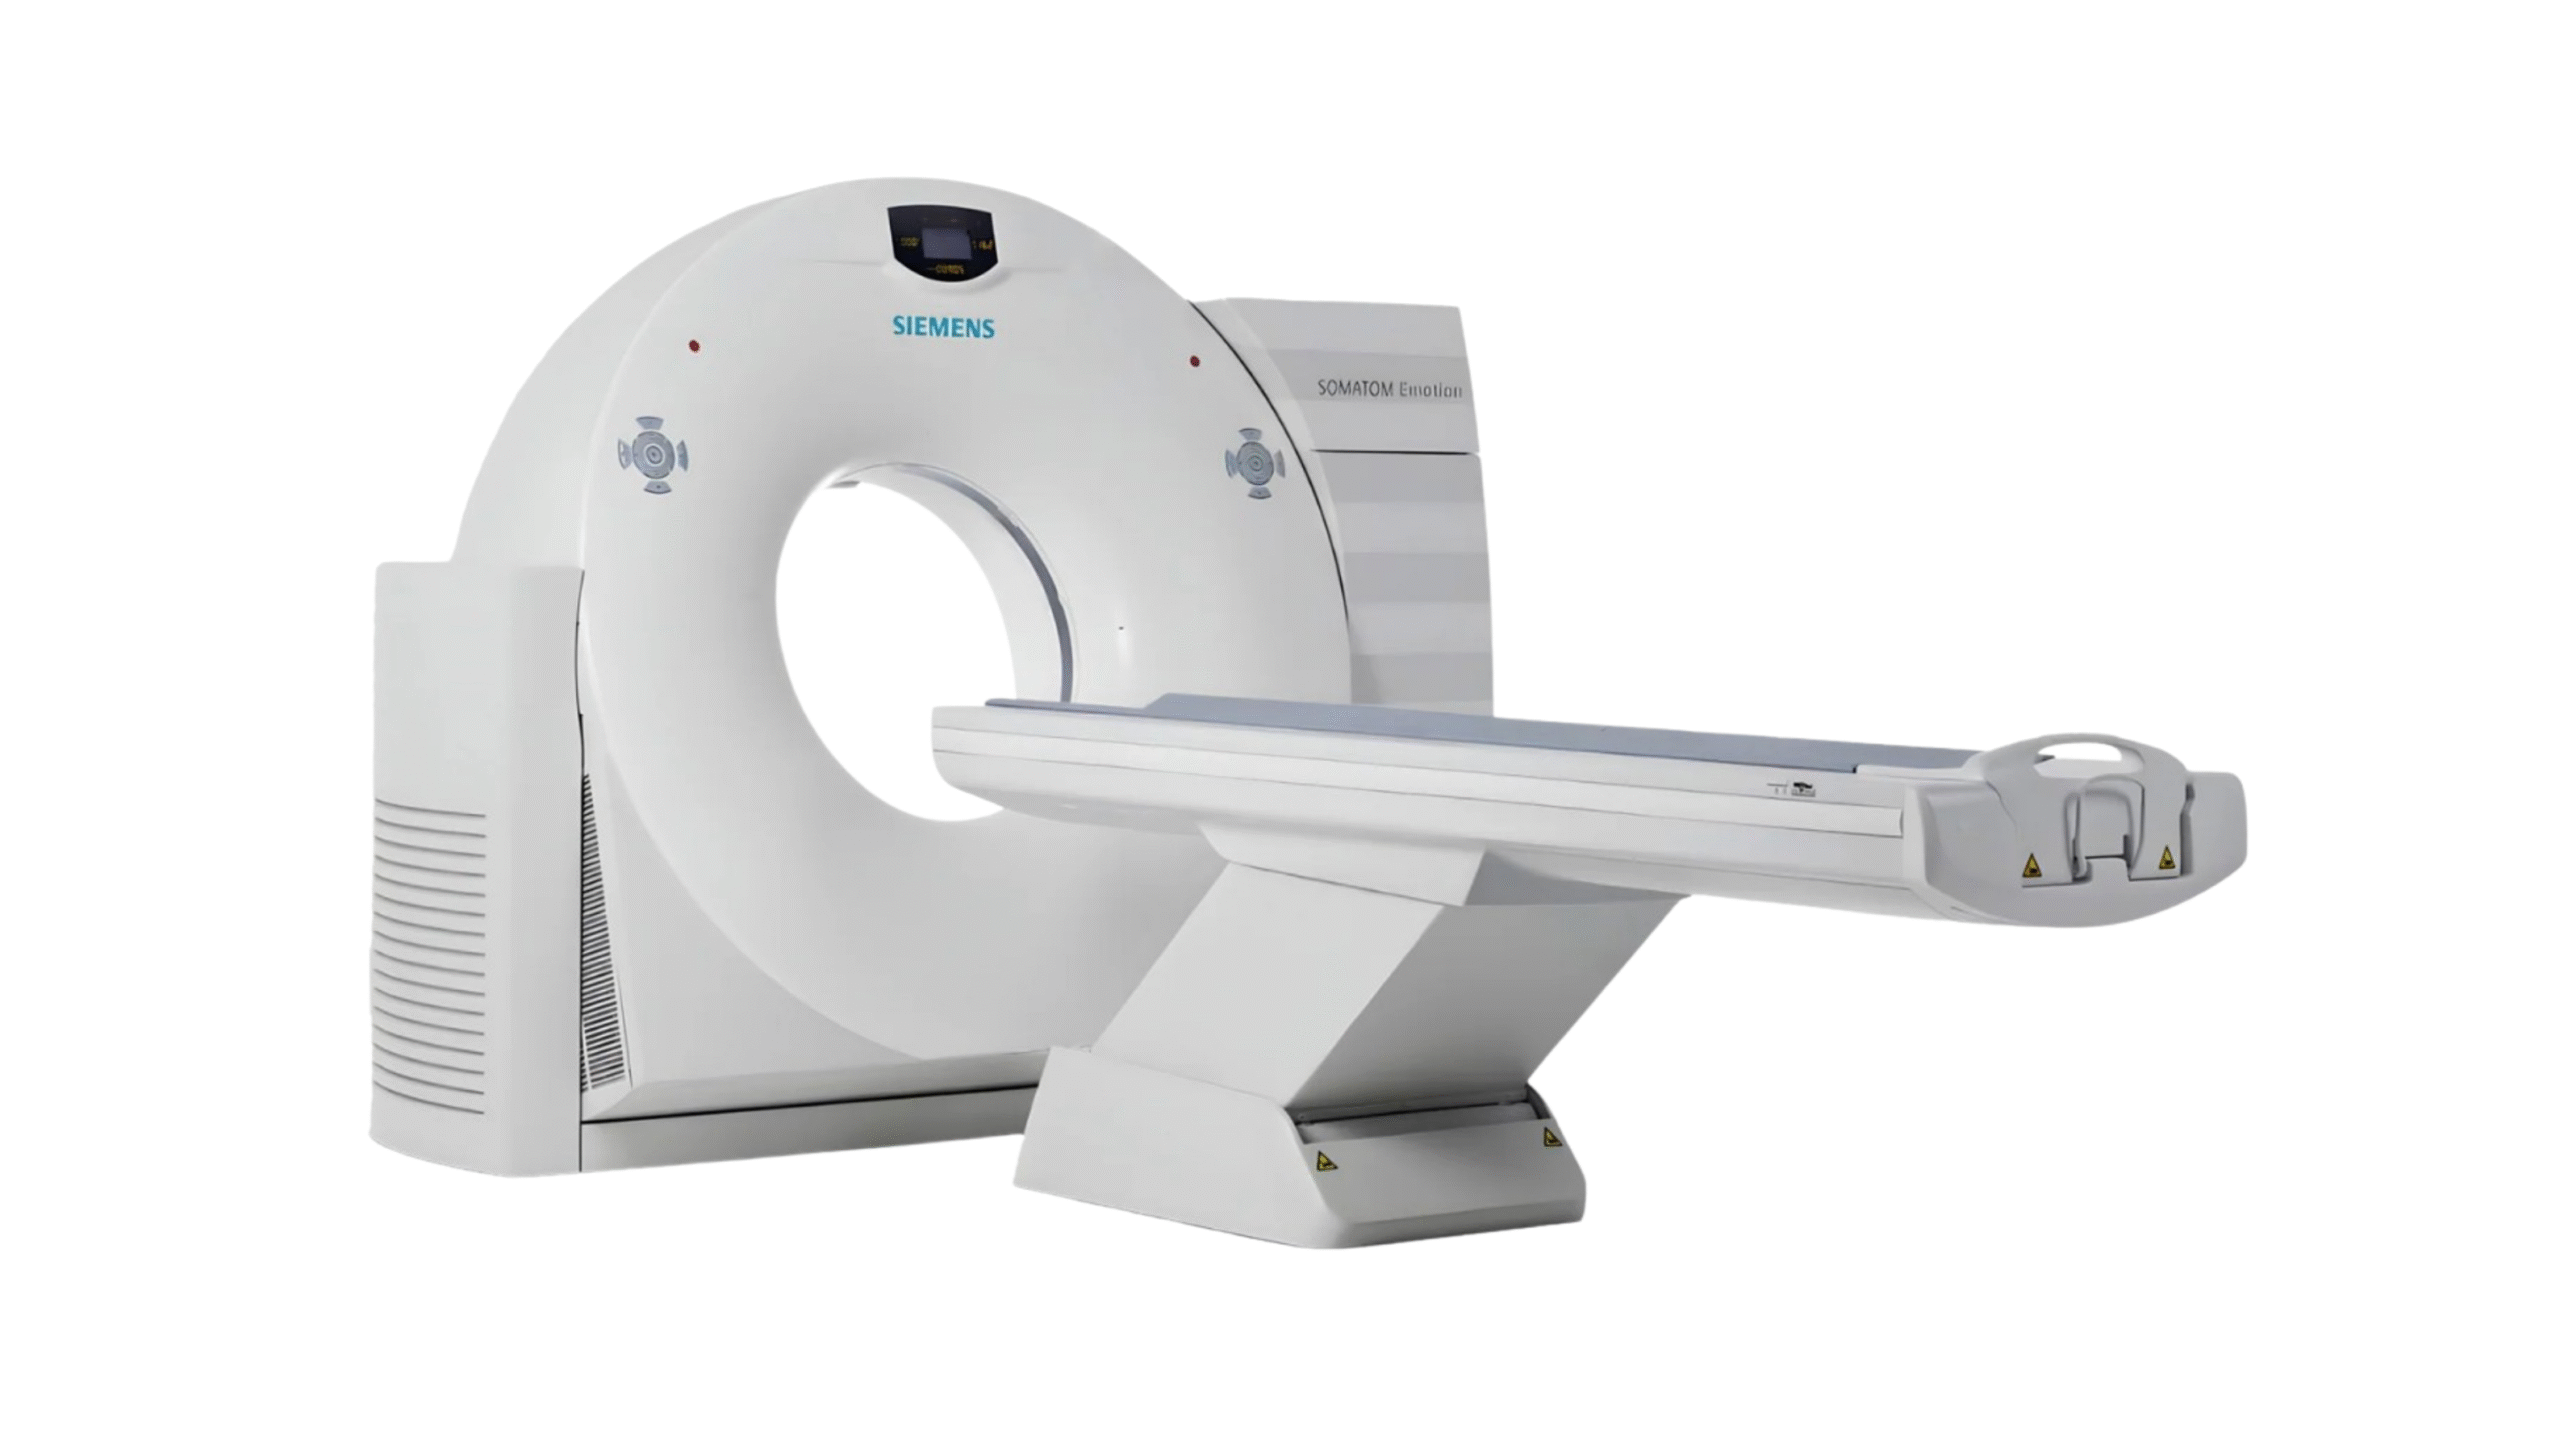

Products